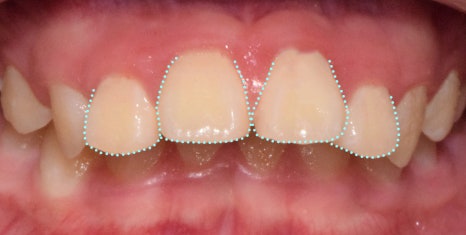

치아나 잇몸뼈 자체가 튀어나온 것을

돌출입이라 부르며,

2급 부정교합에 해당하는데요.

위아래 앞니 잇몸과 치아가 전방으로 돌출하여

웃을 때 잇몸이 과하게 보이게 되는 것은 물론이고

입이 ‘잘’ 다물어지지 않습니다.

처음에는

치아가 보이지 않을 정도로

많이 튀어나왔지만,

턱이 뒤로 들어가면서

올바른 형태로 찾아갈 수 있었습니다.